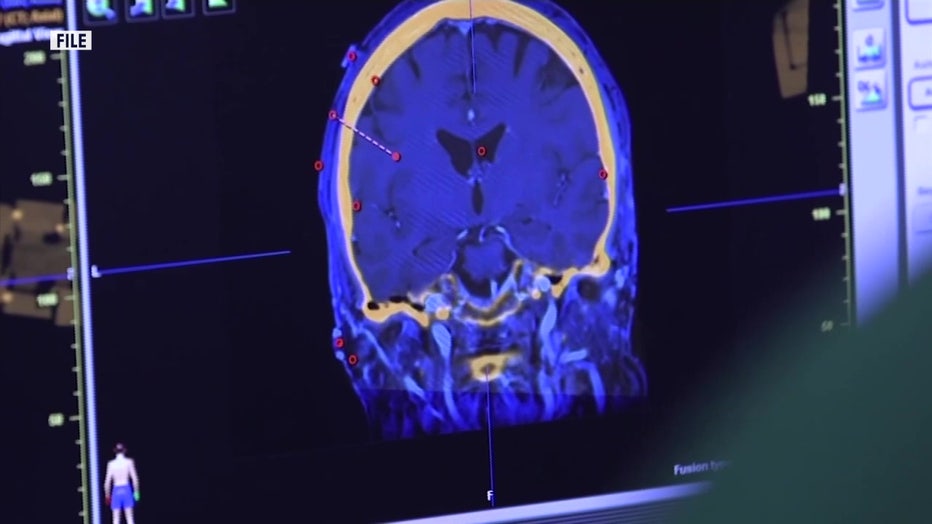

Cole was diagnosed with a malignant tumor in her ovaries that was later identified as an ependymoma, a type of brain tumor. While ependymomas account for about 2% of all brain tumors, their appearance in the ovaries is extraordinarily uncommon.

After further evaluation at Moffitt Cancer Center, Dr. Robert Wenham, chair of the Department of Gynecological Oncology, identified the tumor as an ependymoma, something typically found in the brain, not the ovaries.

Doctors believe the tumor likely developed within a teratoma, a usually benign ovarian tumor that can contain multiple tissue types, including, in rare cases, neurological tissue. "This is the kind of case that someone only sees maybe once in their career," Wenham said.